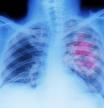

Se invitará a participar a personas que hayan fumado un paquete de tabaco diario durante 20 años o una cantidad equivalente (por ejemplo, medio paquete durante 40 años). Se les realizará un TAC de baja dosis para detectar cánceres de pulmón cuando aún se puedan extirpar con cirugía y las perspectivas de curación sean elevadas. La prueba se repetirá anualmente.

Se ofrecerá un TAC anual a personas de 50 a 75 años que hayan fumado un paquete diario durante 20 años, o una cantidad equivalente